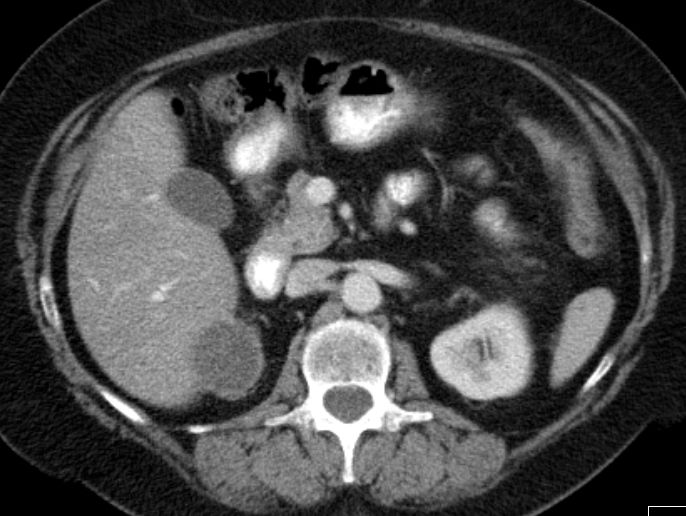

GIST der rechten Magenwand![]() |

56-jähriger Mann mit großer Raumforderung der Magenvorderwand.

Gallenblase und Leber werden etwas verdrängend.

Vergrößerte Lymphknoten sind nicht nachweisbar.![]() | |||||||||||||||||||||||||||||||||||||||||